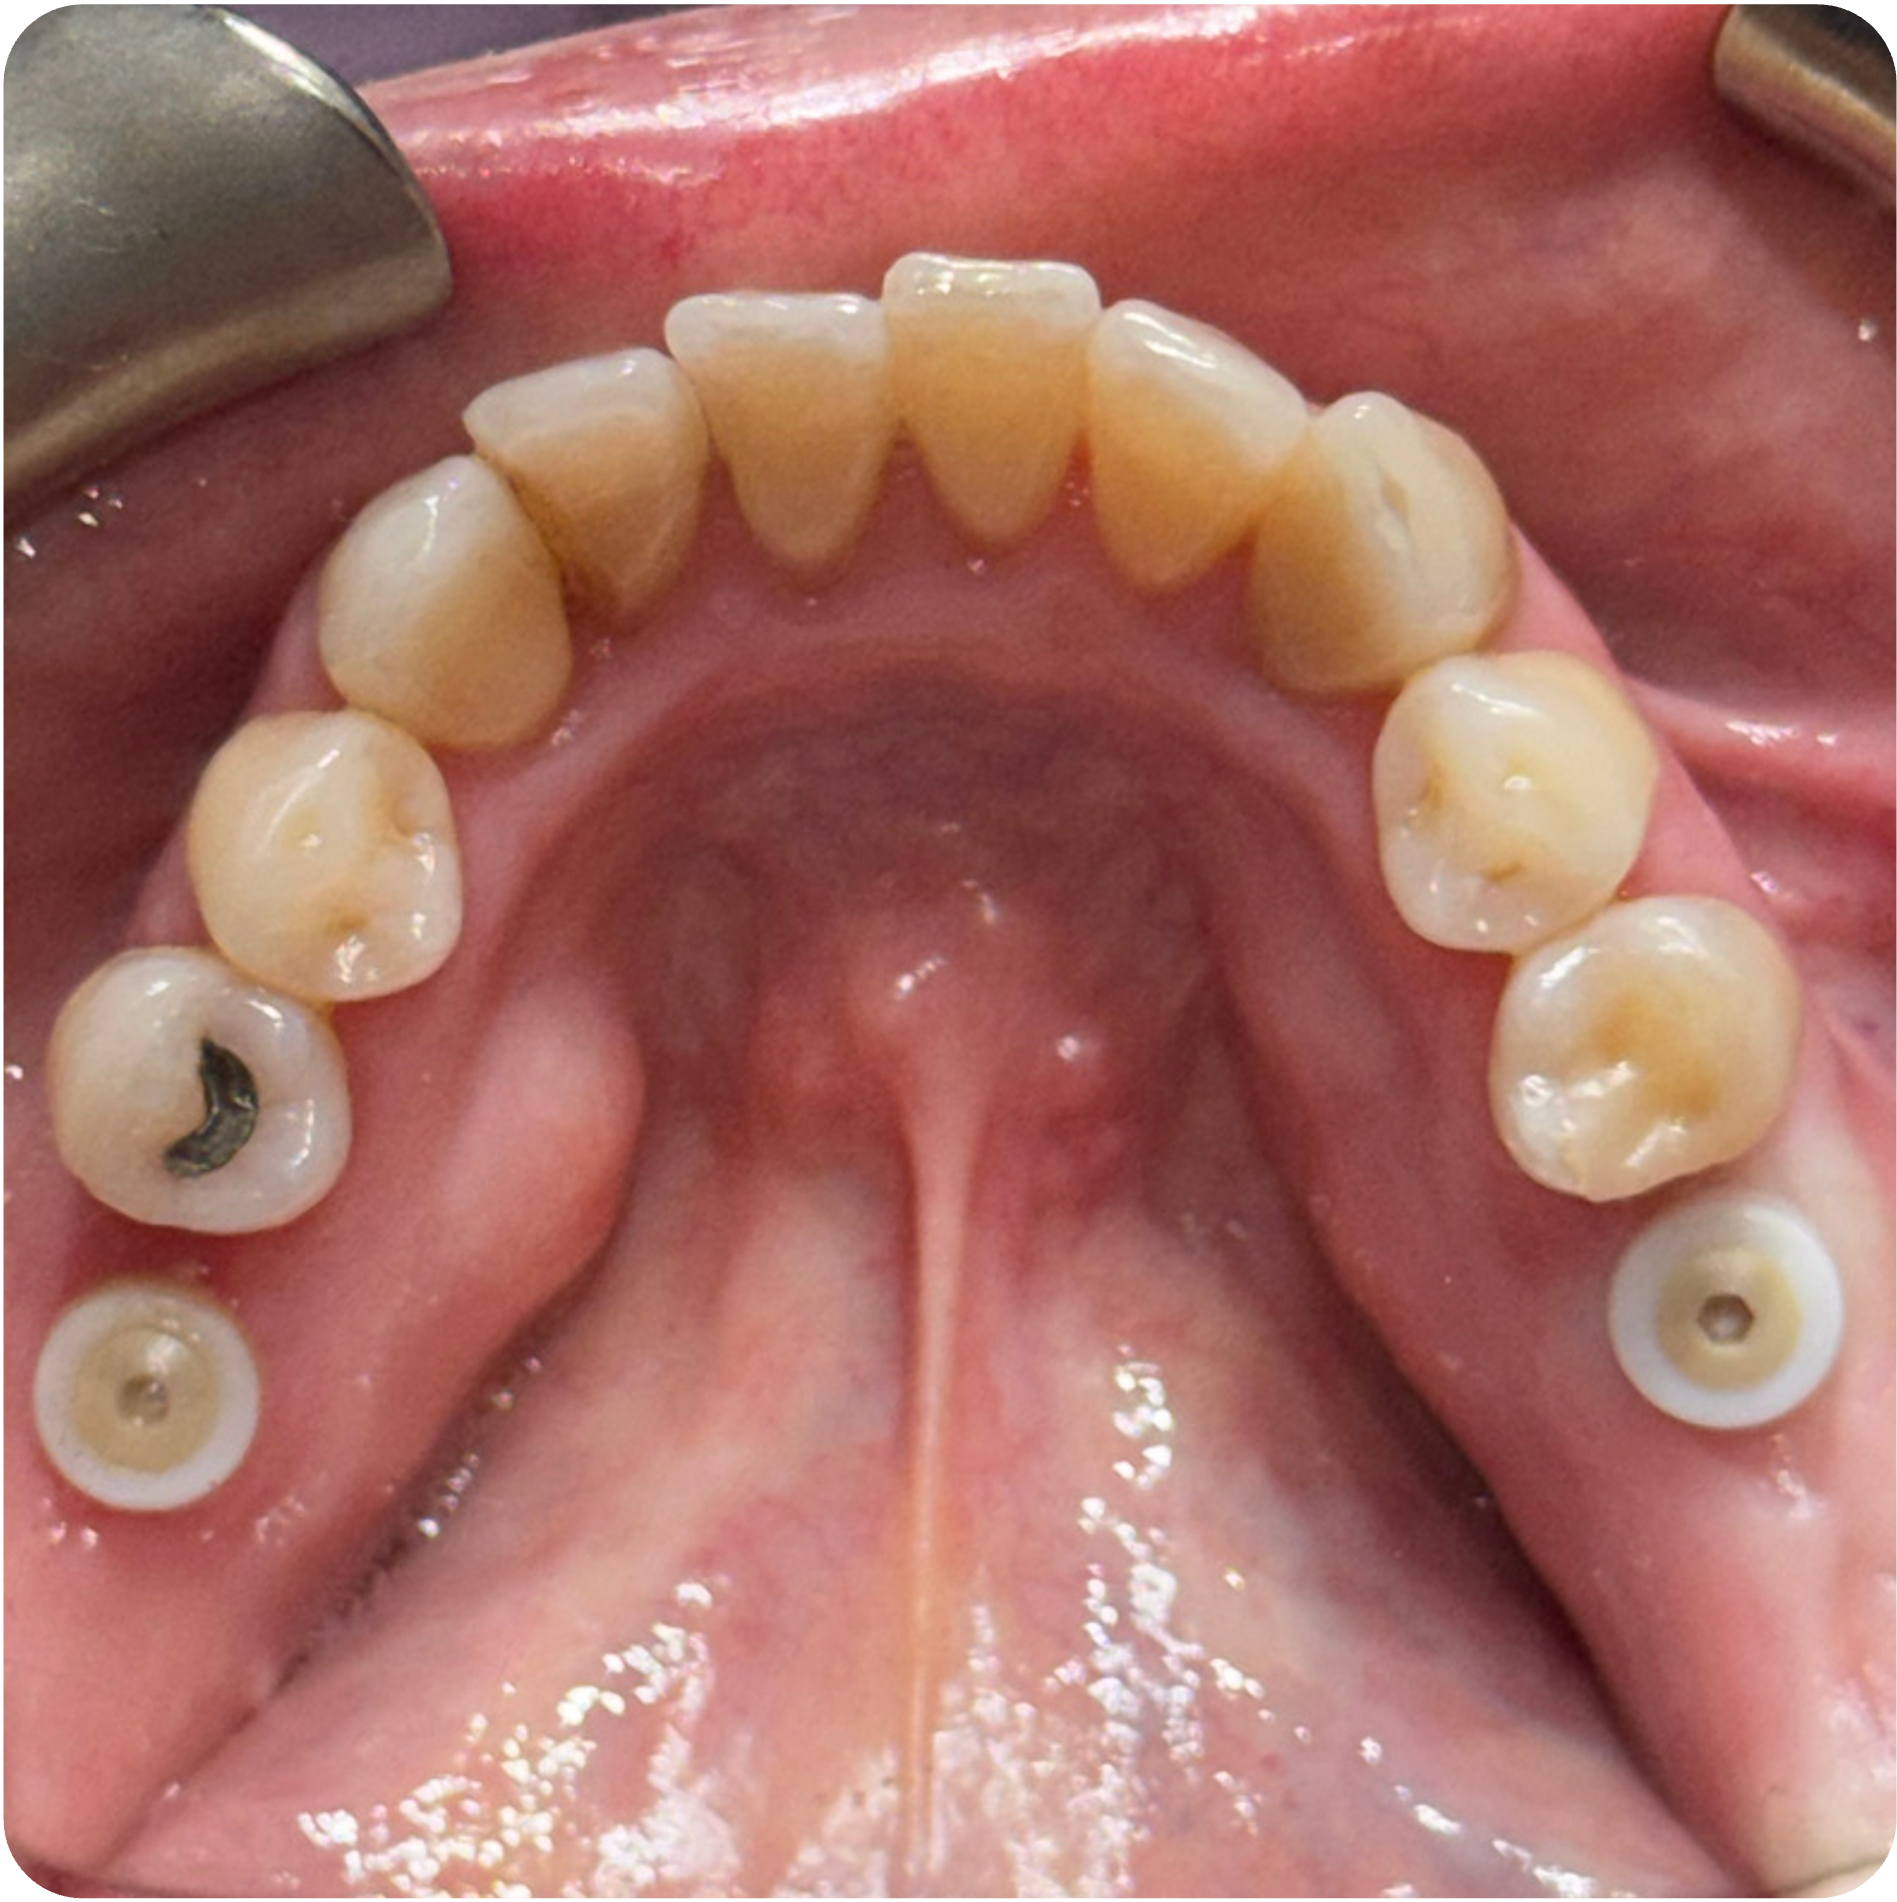

November 26, 2025Implant placement (#3 and #30).

December 02, 2025Implant placement (#14 and #19).

Visual Case Progression

All clinical images are shown at a consistent size for easy comparison.

- Implant Placement in Stabilized Sites: Once infection was controlled and bone matured, implants were placed in #3, #30, #14, and #19 to restore function and long-term structural integrity.